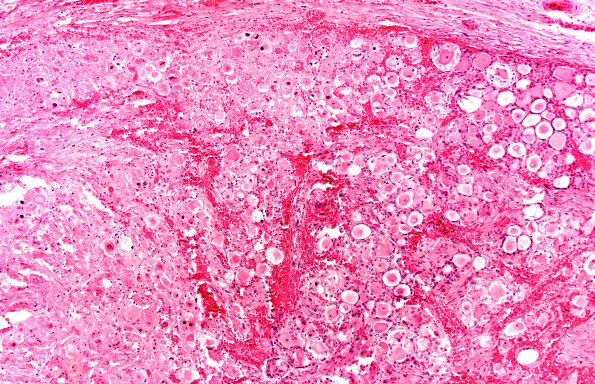

Washington University Experience | PERIPHERAL NEUROPATHY | 10 INFECTION | 1 Herpes Zoster | 2A2 Zoster DRG (Case 2) H&E 10X 1a

Higher magnification of image #2A1 showing a large area of necrosis on the left margin of the image. (H&E)